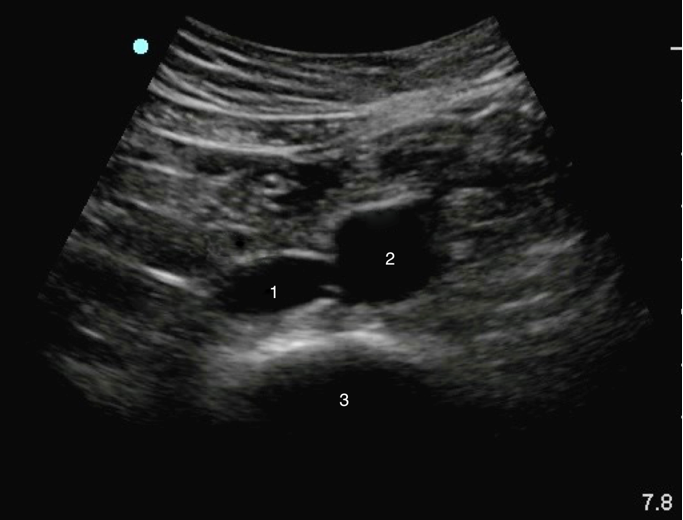

Distal Aorta Image

Inferior Vena Cava (IVC)

Aorta

Spine